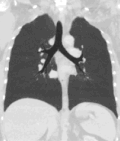

Lungs

[edit]A CT scan can be used for detecting both acute and chronic changes in the lung parenchyma, the tissue of the lungs.[41] It is particularly helpful because normal two-dimensional X-rays do not show such defects. A variety of techniques are used, depending on the suspected abnormality. For evaluation of chronic interstitial processes such as emphysema, and fibrosis,[42] thin sections with high spatial frequency reconstructions are used; often scans are performed both on inspiration and expiration. This special technique is called high resolution CT that produces a sampling of the lung, and not continuous images.[43]

Bronchial wall thickening can be seen on lung CTs and generally (but not always) implies inflammation of the bronchi.[44]

An incidentally found nodule in the absence of symptoms (sometimes referred to as an incidentaloma) may raise concerns that it might represent a tumor, either benign or malignant.[45] Perhaps persuaded by fear, patients and doctors sometimes agree to an intensive schedule of CT scans, sometimes up to every three months and beyond the recommended guidelines, in an attempt to do surveillance on the nodules.[46] However, established guidelines advise that patients without a prior history of cancer and whose solid nodules have not grown over a two-year period are unlikely to have any malignant cancer.[46] For this reason, and because no research provides supporting evidence that intensive surveillance gives better outcomes, and because of risks associated with having CT scans, patients should not receive CT screening in excess of those recommended by established guidelines.[46]